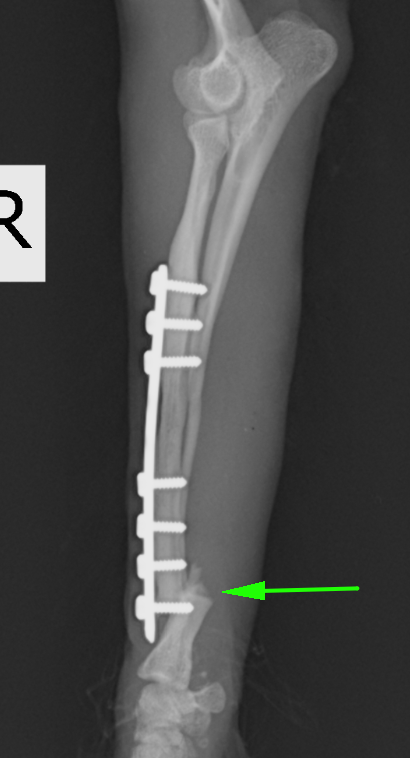

次の症例は以前の骨折を他院にてプレート固定していたそうですが、ある時からまた足を上げるとのことで来院しました。矢印の部分で折れてしまっています。

入っていたプレートを抜去したところです。入っていたところの遠位(左写真の左側)に骨折線があります。プレートのスクリューホールに骨が入り込むのでボコボコとした形になります。

今回の手術後の写真です。非常に長いプレートが入っているのは、手術して再骨折があった場合にはもとのプレートよりも長いプレートを入れる必要があるからです。また、骨が痩せて細くなっているケースが多いので術後も注意が必要です。